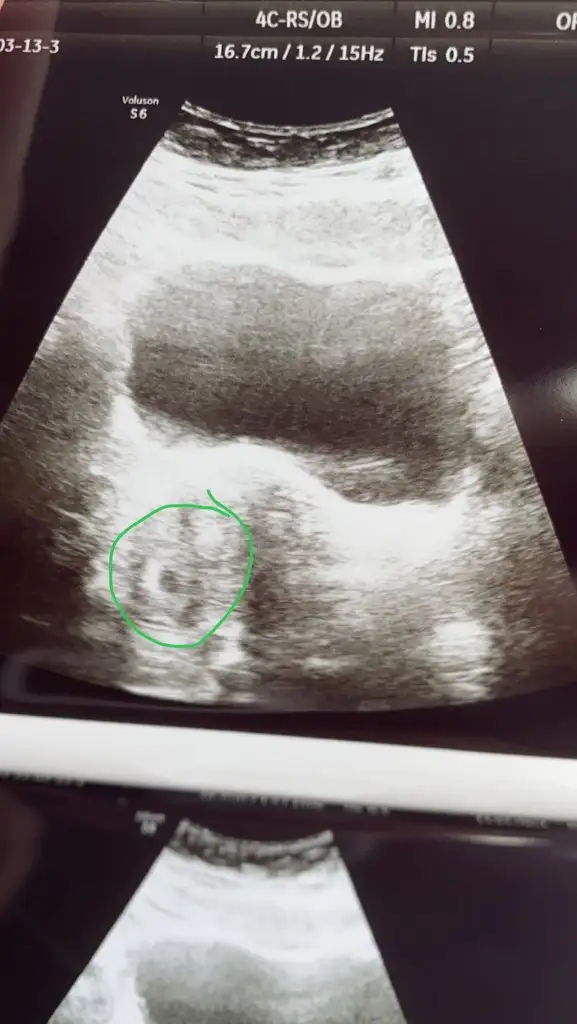

Bunun üzerine 10 martta doktora gittim ve bhcg 4430 çıktı . fakat kese yoktu

13 martta tekrar gittik ve ekteki şekilde minik bir keseye benzettiği görüntü çıktı fakat yine yolk vs yoktu .

10 gün sonra tekrar gel dedi ama içim içimi yiyor

Karından yapıldı vajinal acele etmeyelim dediMerhaba, Vajinal muayene mi acaba? Bir de baska doktora gitseniz iyi olacak gibi sanki

Karından gorunmeyebiliyor, ilk zamanlar vajinadan bakmak daha iyi, net olyor o zaman, hem de dis gebelik vs onlar daha iyi saptanabiliyor aslinda. Istersen baska doktora bir git, vajinal bakilsin hem.Karından yapıldı vajinal acele etmeyelim dedi